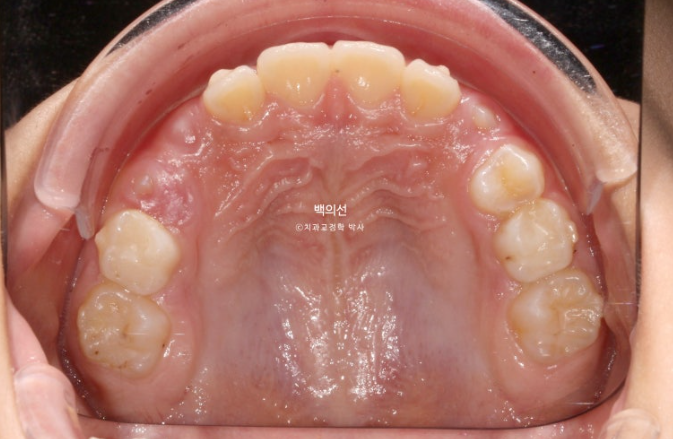

25.07

이제 남아있는 유치는 없고 모든 영구치가 제자리에 예쁘게 나왔습니다.

물샐틈 없는 1급 교합관계를 보입니다.

결과가 성인 2차교정결과에 준하는 만큼 유지장치도 성인교정 유지장치와 동일하게 들어갑니다.